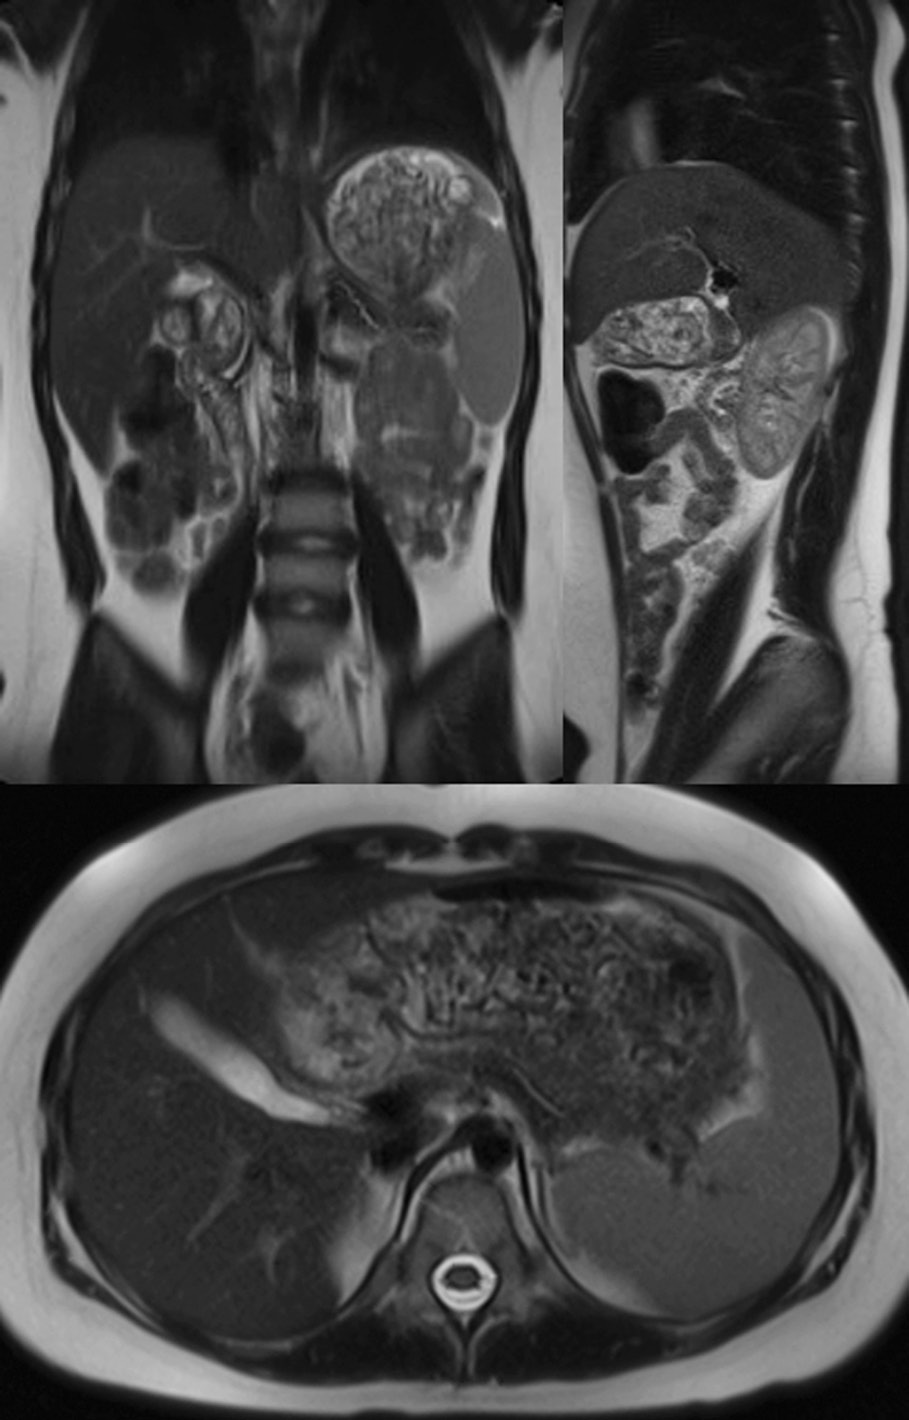

Девочка, 10 лет, поступила в ЦРБ по месту жительства с жалобами на постоянные тянущие боли в эпигастрии давностью трое суток, тошноту, рвоту съеденной пищей, фебрильную лихорадку. При УЗИ органов брюшной полости, выполненном в приемном отделении, — признаки отека паренхимы поджелудочной железы, на уровне хвоста жидкостное однородное скопление неправильной формы размерами 82 × 46 × 30 мм. Течение острого панкреатита также подтверждено параклинически. Из анамнеза ребенка известено о приеме препаратов вальпроевой кислоты с возраста 11 мес. в связи с имеющейся эпилепсией. Назначена инфузионная терапия, спазмолитики, антибактериальная терапия. На следующие сутки ребенок переведен в детское хирургического отделение ГНОКБ. При поступлении выполнена МСКТ органов брюшной полости с внутривенным болюсным контрастированием, выявлены признаки панкреонекроза с прорывом главного панкреатического протока и образованием острого жидкостного скопления по передней поверхности хвоста и тела поджелудочной железы до 7 см в диаметре, оттесняющего желудок кпереди, выраженный отек всех отделов поджелудочной железы, контрастирование паренхимы неоднородное. Отек парапанкреатической клетчатки с распространением в ворота селезенки, вдоль переднего листка фасции Герота слева и левого бокового канала (рис. 4).

Рис. 4. Мультиспиральная компьютерная томография. Венозная фаза органов брюшной полости. Стрелки указывают на жидкостное перипанкреатическое образование